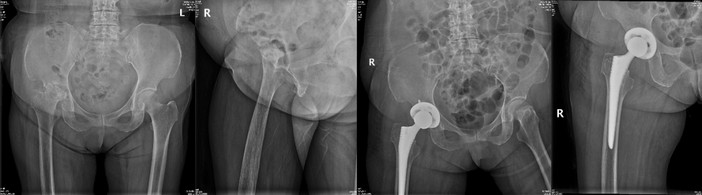

手術(shù)治療

許×,女,66歲,嚴重股骨頭壞死并髖骨關(guān)節(jié)炎行人工全髖關(guān)節(jié)置換術(shù),術(shù)后3天下地,1周上下樓梯。